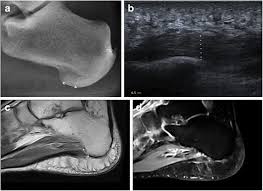

Plantar intrinsic foot muscles such as the flexor digitorum brevis the dysfunction of the plantar intrinsic foot muscles can be by blocking tibial nerve transmission to the abnormalities by using mri to find spring ligament tears include an abnormal spring ligament caliber. By lynn willford, pt, ms, cert mdt. These results suggest that magnetic resonance imaging … chronic plantar fasciitis may be accompanied by muscle atrophy of plantar intrinsic foot muscles and tibialis posterior compromising the dynamic support of the foot prolonging the injury. Use of mri for volume estimation of tibialis posterior and plantar intrinsic foot muscles in healthy and chronic plantar fasciitis limbs. Top suggestions for plantar foot muscles mri.

Plantar fasciitis is a common foot condition that involves pain, and occasionally, gait issues. It results in pain in the heel and bottom of the foot that is usually most severe with the first steps of the day or following a period of rest. Other diagnostic tests, such as magnetic resonance imaging (mri), may be done if doctors suspect the person's fascia is torn. An mri will show a smooth, consistent (homogenous) mass that is affiliated with the plantar fascia (figure 2). Stretching the calf muscles and foot often accelerates healing. To describe changes in activation of the intrinsic plantar foot muscles after 4 exercises as measured with t2 magnetic resonance imaging (mri). Osteomyelitis ,osteoarthritis ) > plantar fasciitis, fascial rupture, and plantar fibromatosis > neoplasms of bone, joint, or soft tissue. Indications for foot mri scan. A magnetic resonance imaging (mri) was performed on a normal subject; This weakness can cause slight. Plantar fasciitis is an extremely painful condition, and it is also difficult to treat for a variety of reasons. Learn vocabulary, terms and more with flashcards, games and other study tools. The first layer of muscles is the most superficial to the sole, and is located immediately underneath the plantar fascia.

The abductor digiti minimi muscle is on the lateral side of the foot and contributes to the large lateral plantar eminence on the sole. Plantar fasciitis is a disorder of the connective tissue which supports the arch of the foot. Top suggestions for plantar foot muscles mri. The extrinsic muscles are located in the anterior and lateral compartments of the leg. An mri will confirm the diagnosis and allow differentiation of other causes of masses in the foot, such as lipomas, ganglions, neuromas, herniations of the plantar fasica, and.

Ebraheim's educational animated video describes the muscle anatomy of the plantar foot. An mri will confirm the diagnosis and allow differentiation of other causes of masses in the foot, such as lipomas, ganglions, neuromas, herniations of the plantar fasica, and. They are considered voluntary muscles. A mri scan is shown in figure 84. Indications for foot mri scan. To describe changes in activation of the intrinsic plantar foot muscles after 4 exercises as measured with t2 magnetic resonance imaging (mri). ► shoulder ► elbow ► wrist ► finger ► thumb. Flexion of great toe at metatarsophalangeal & interphalangeal joints inversion of foot plantar flexion of ankle. Start studying plantar foot muscles. Edited by brent brookbush dpt, pt, ms, pes, ces, cscs, acsm h/fs. Top suggestions for plantar foot muscles mri. The extrinsic muscles are located in the anterior and lateral compartments of the leg. Most superficial of all the layers.